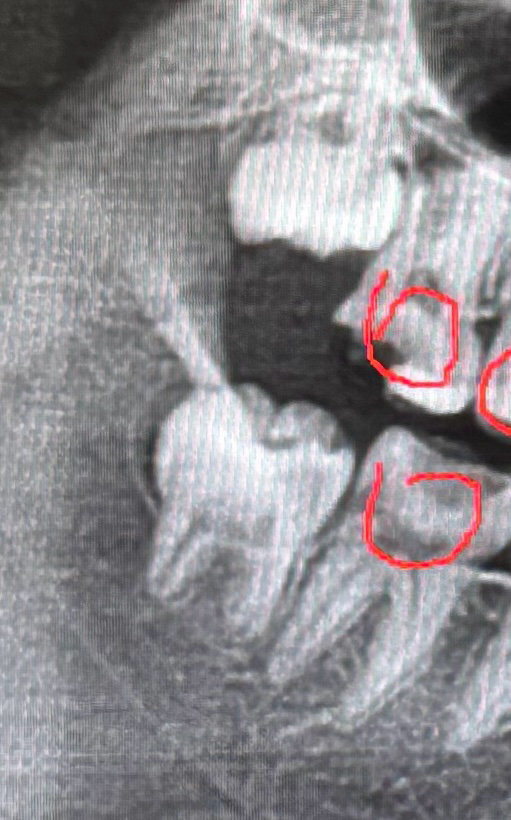

맨 끝 어금니 크라운 하기 위해서 사랑니를 발치해야한다고 하시던데 전 사랑니가 누워있는 상태도 아닌데 왜 발치해야하나요? 꼭해야하나요? 발치 안하고 크라운 하면 사랑니가 나중에 나올 때 크라운을 방해하나요? 22살입니다

22살이라면 사랑니가 더 맹출되거나 하진 않을것같습니다. 위쪽은 발치를 안해도 될꺼 같지만 아래쪽은 사랑니 발치를 하시는게 관리차원에서 좋을것같습니다.

위 사랑니는 지금보다 조금 더 내려올 확률이 있고 아래 사랑니는 방향은 괜찮으나 턱뼈에 걸려서 여기서 더이상 움직이지 않을 가능성도 있습니다 두번째 어금니 크라운을 씌울때 관리의 용이성을 위해 사랑니를 빼는 경우가 있습니다